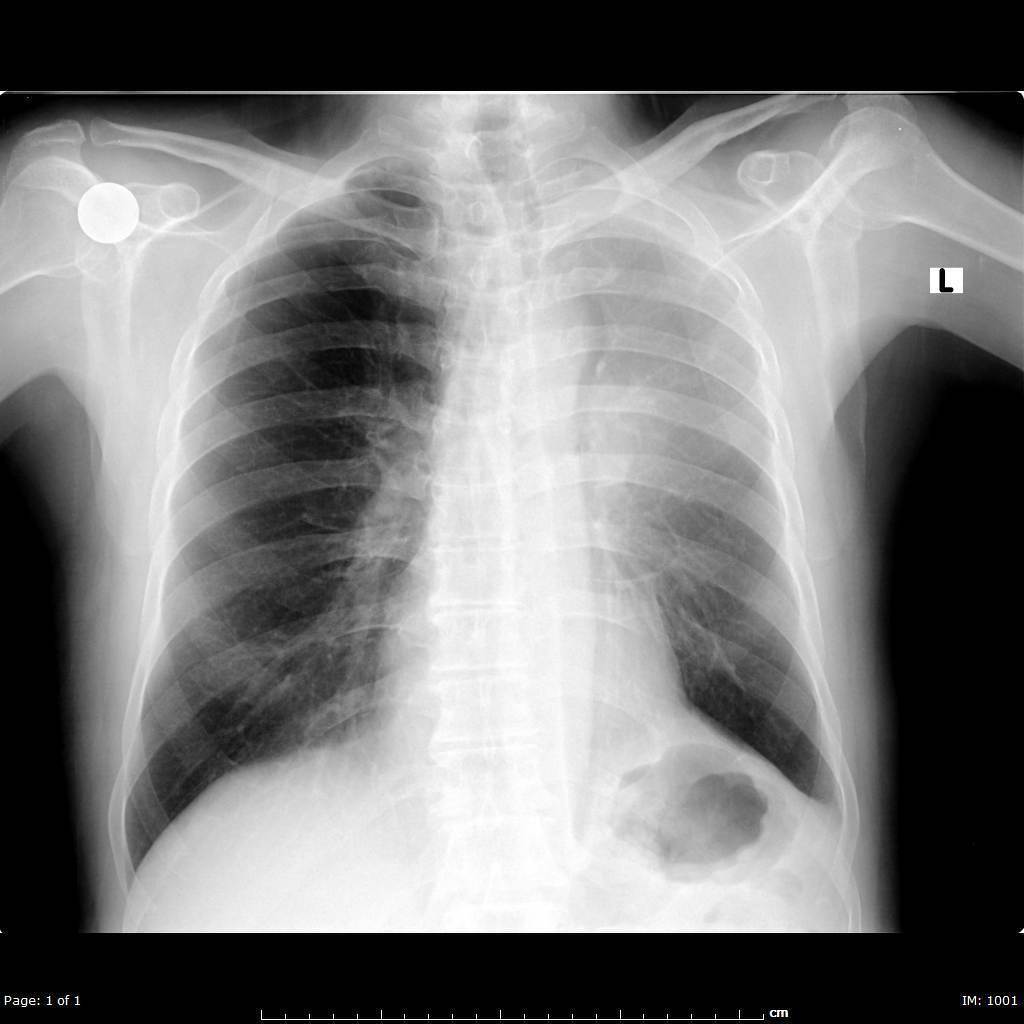

Atelectasis

Loss of lung volume due to decreased aeration. Synonymous with collapse. Direct signs of atelectasis are from lobar volume loss and include: displacement of the fissures and vascular crowding. Indirect signs include elevation of the diaphragm, rib crowding on the side with volume loss, mediastinal shift to the side with volume loss, overinflation of adjacent or contralateral lobes, hilar displacement. Air bronchograms are not seen in atelectasis when the cause of the atelectasis is central bronchial obstruction, but air bronchograms can be seen in subsegmental atelectasis. Subsegmental atelectasis is caused by obstruction of small peripheral bronchi, usually by secretions.

Lobar Atelectasis

Usually caused by central broncial obstruction (obstructive atelectasis), which may be secondary to mucus plugging or an obstructing neoplasm. If the lobar atelectasis occurs acutely, mucus plugging is the most likely cause. If lobar atelectasis isseen in outpatient, an obstructing central tumor must be ruled out. Lobar atelectasis, or collapse of an entire lobe, has characteristic appearances depending on which of the five lobes is collapsed.